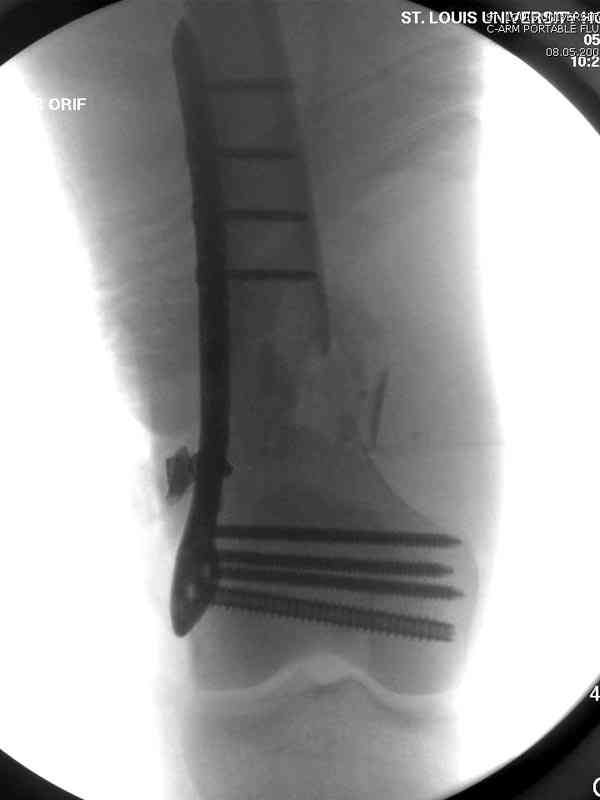

Огнестрельный перелом бедра

Вдогонку к обсуждению случая несращения дистального отдела бедра 9 мая утром поступил больной с огнестрельной раной, осмотрен сосудистым специалистом, сделана ангиограмма (снимки)

Во время операции при вскрытии обнаружили кровотечение, рану забили салфетками, установили пластину locking DePuy.

Из-за возрастающего давления в компартменте сделана фасциотомия и вызванный сосудистый хирург ушил разрыв вены на уровне перелома. Все раны оставлены открытими, в пятницу закроем.